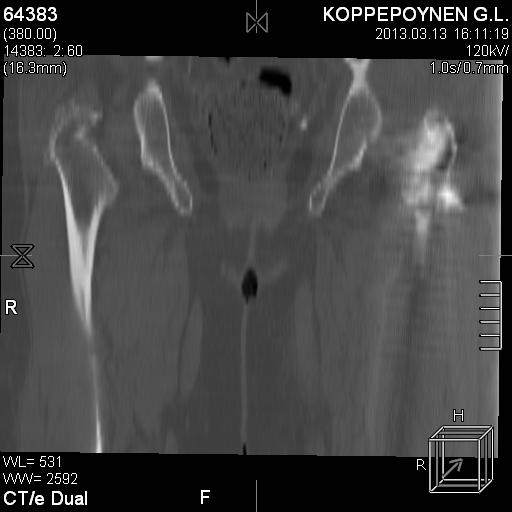

[Ortho] Чрезподвертельный перелом бедра. Остеосинтез стержнем. Перелом металлофиксатора. Дальнейшая тактика?

Делали КТ после операции.